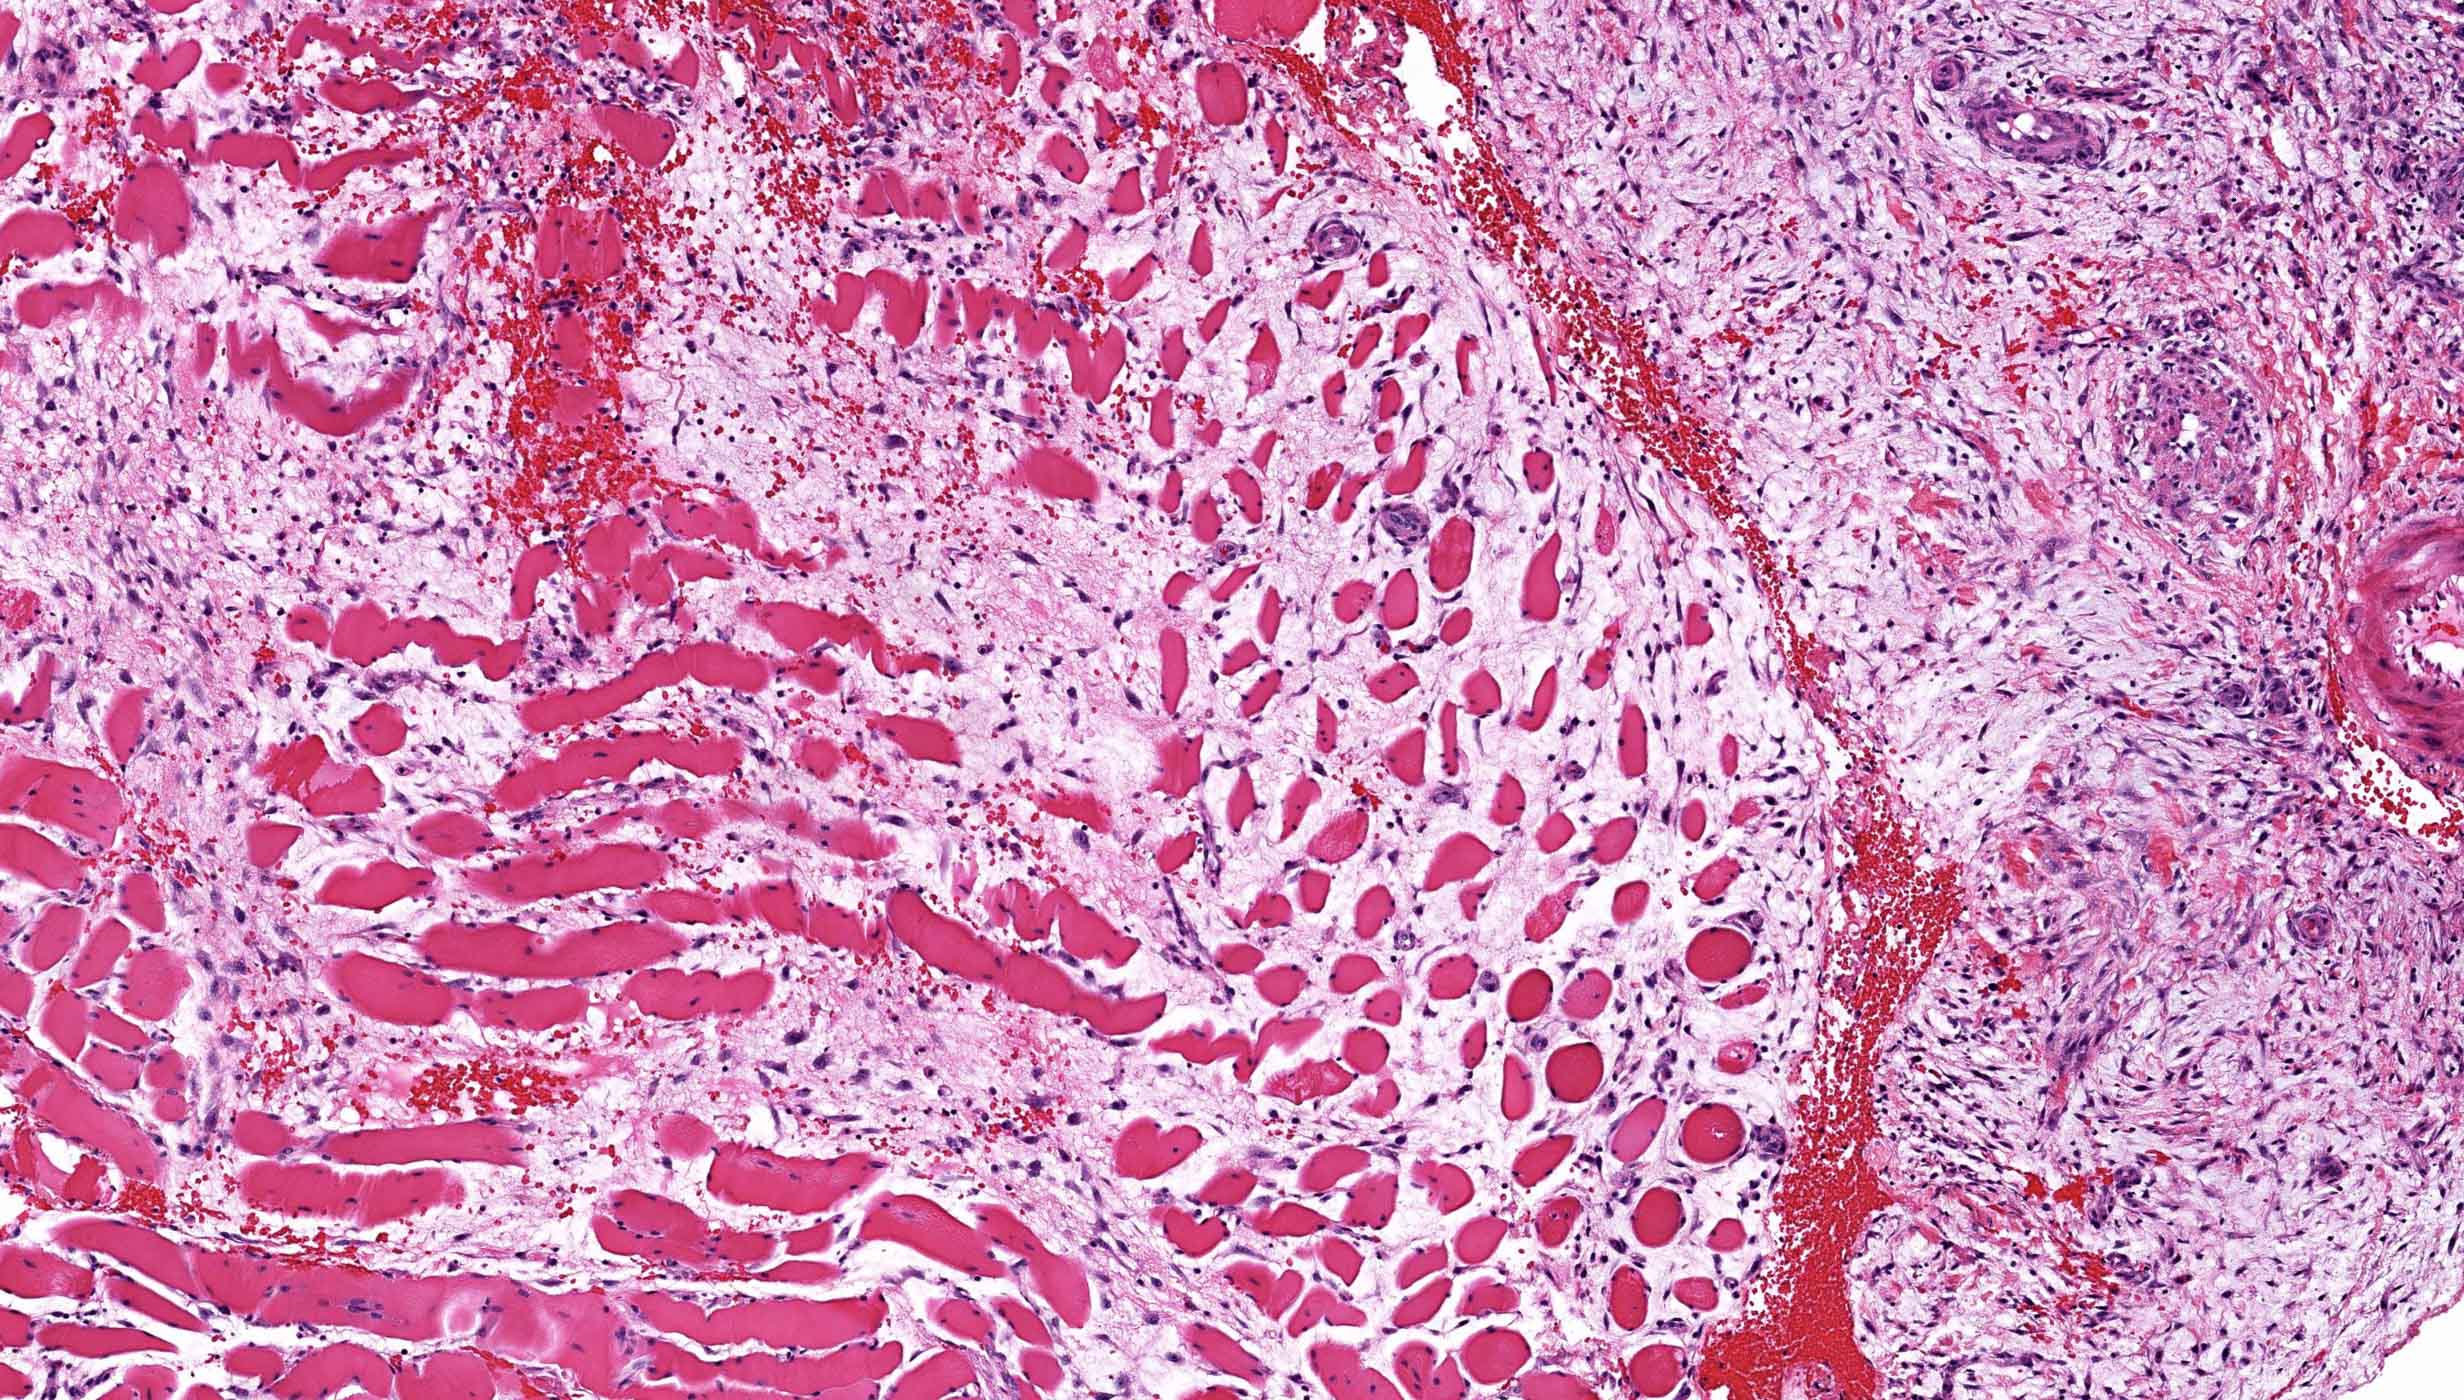

- Histologically, zonal pattern is characteristic with different degrees of cellular differentiation (inner zone, intermediate zone and peripheral zone)

- Areas of hemorrhage, fibrin, endothelial proliferation and entrapped atrophic muscle fibers are noted

- Peripheral zone:

- Osteoid undergoes calcification and leads to lamellar bone formation

- Islands of mature or immature cartilage may be present

- Extreme periphery / margin shows mature bone with osteoblastic rimming and little to no pleomorphism

- Lesion is separated from the normal tissue (muscle) by a zone of loose, myxoid fibrous tissue

Microscopic (histologic) images